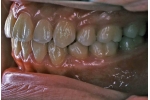

| 治療前後の比較